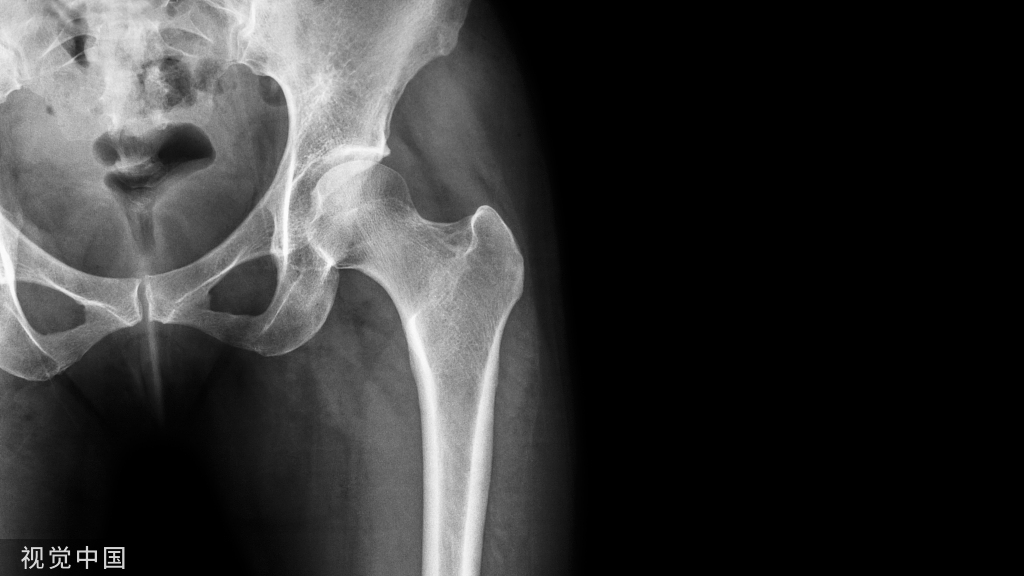

大腿骨折

1、夹板固定法:伤者仰卧,伤肢伸直。用两块夹板分别放在大腿内、外两侧。外侧夹板长度从腋窝至足跟,内侧夹板长度从大腿根部至足跟(如果只有一块夹板则放于大腿外侧,将健肢当作内侧夹板),关节处与空隙部位加衬垫;然后用布带固定骨折部位的上、下两端,再分别固定胸部、腰部、膝部、踝部,踝部与足部应采用“8”字形固定,以免伤侧足部外旋。

大腿骨折,打结顺序:① 踝关节与足部、② 膝关节下、③ 靠近骨折部位近上端、④ 靠近骨折部位近下端。

2、健肢固定法:无夹板时,可用布带将伤肢与健肢固定在一起,两膝与两踝之间应加衬垫,先固定骨折部位上、下两端,再固定膝关节以上与踝关节处,踝与足部应采用“8”字形固定(参看“夹板固定法”)。